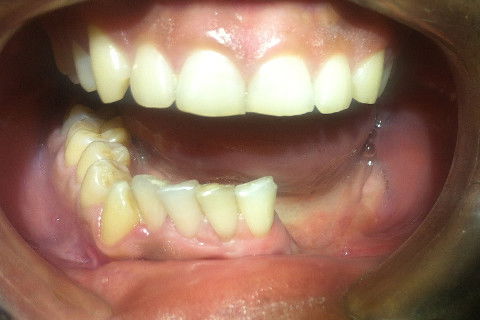

Vista Frontal

Paciente do sexo masculino, 25 anos, procurou o serviço de Cirurgia e Traumatologia Buco Maxilo Facial, apresentando ao exame clinico: aumento de volume em região esquerda da face com histórico evolutivo há 2 anos, assintomático. Ao exame de RX panorâmico dos maxilares, apresentava lesão cística comprometendo os elementos dentários 36, 37 e 38. Ao exame de Tomografia Computadorizada da face, foi evidenciado expansão das corticais ósseas mandibulares, com comprometimento de toda tábua óssea da região. Realizada biopsia incisional em primeiro tempo, com laudo conclusivo de Tumor Odontogênico " Ameloblastoma". Foi submetido a novo procedimento cirúrgico de Madibulectomia parcial do corpo e ramo mandibular, através do acesso cervical submandibular, seguido de reconstrução com Placa em Titânio, sistema 2.4mm. Com 2 meses de pós operatório, encontra-se sob tratamento reabilitador fisioterápico e Fonoterápico, com excelente evolução clínica e funções estomatognáticas mantidas. Será submetido a novo procedimento cirúrgico para reconstrução do defeito ósseo, através de enxerto autógeno retirado da crista Ilíaca e preparado com PRP após 6 meses.